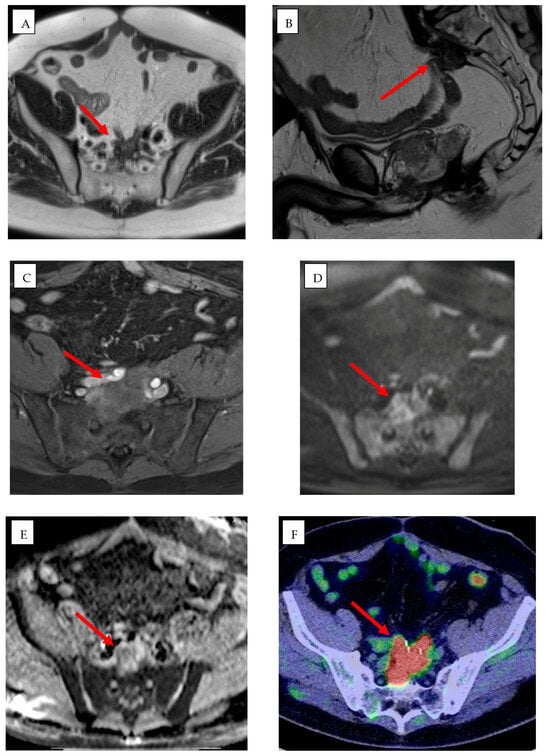

AI-driven image guidance systems such as XperGuide (Version 3.5.1, Philips Allura Xper FD20, Philips Healthcare), improve the precision of percutaneous procedures by delivering real-time three-dimensional needle guidance for percutaneous interventions [,] (Figure 3). XperCT software (Version 3.5.1, Philips Allura Xper FD20, Philips Healthcare) can be used to predict ablation volume [].

Figure 3.

A 61-year-old man with rectal adenocarcinoma previously treated with surgery, adjuvant chemotherapy, and radiotherapy. Pre-procedural MRI, including axial (A) and sagittal (B) T2-weighted images, (C) T1-weighted post-contrast image, and (D) diffusion-weighted imaging (DWI) with (E) apparent diffusion coefficient (ADC) map, together with (F) 18F-FDG PET/CT, demonstrate a heterogeneous mass in the presacral region consistent with local disease recurrence (red arrows). (G–I) Intra-procedural cone-beam CT (CBCT) in axial (G), coronal (H), and sagittal (I) planes obtained using XperGuide software (Philips Healthcare) for cryoablation probe placement (purple arrows), and XperCT (Philips Healthcare) for ablation zone prediction (purple and yellow circles).

XperGuide and XperCT are utilized in a wide variety of clinical settings, particularly in liver, lung, and renal tumor interventions. In liver tumors, particularly those located in the subphrenic region or near vital structures, their precise needle placement capabilities reduce the need for intraoperative patient repositioning and significantly lower the risk of complications such as infection and misplacement []. Similarly, in lung interventions, XperGuide enhances the accuracy of needle navigation in complex thoracic anatomies, thereby decreasing the number of passes required, reducing the risk of pneumothorax, and minimizing procedural trauma and subsequent interventions [,]. For renal tumors and spinal metastases, XperCT improves lesion visibility in areas where MRI may be limited, enabling more precise treatment planning and needle placement [,].

Both XperGuide and XperCT use intelligent algorithms for real-time trajectory optimization, motion compensation, and collision detection, but are not fully dependent on deep learning. These features enhance the safety of procedures by considering the patient movements—such as breathing—and avoiding important structures. Moreover, ongoing research seeks to integrate ML models that predict lesion response based on ablation geometry, suggesting optimal energy settings tailored to specific tissue characteristics. This would further personalize interventions, improving the likelihood of complete tumor ablation while minimizing damage to surrounding healthy tissues [,].